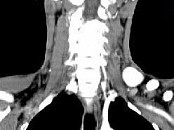

- 单项选择题男,46岁, 外伤后左下颈搏动性肿块,CT如图所示, 最可能的诊断是 ( )

A、左颈部血管瘤

B、左颈动脉体瘤

C、左颈静脉球瘤

D、左颈总动脉假性动脉瘤

E、左颈部动静脉畸形